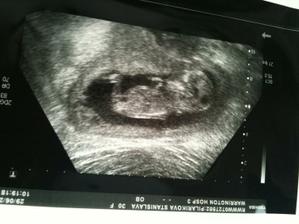

@evelin116 dakujem, to bolo v 20 tyzdni. Pekna fotocka, ale nozicky malo prekrizene, takze nevieme co budeme mat 🙂